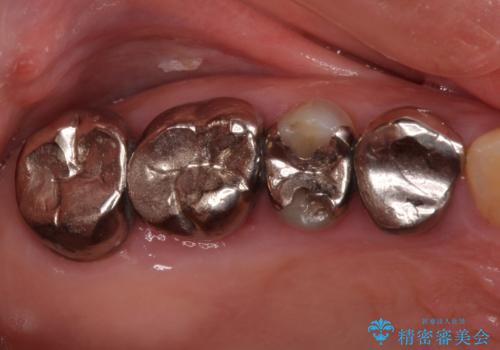

全ての奥歯の銀歯をセラミックに メタルフリー治療

- 奥歯に装着されている銀歯を全て外したいとのことで来院された患者様です。

土台に含まれている金属も含め、奥歯の金属は全て除去し、オールセラミッククラウンやセラミックインレーにて治療することとしました。